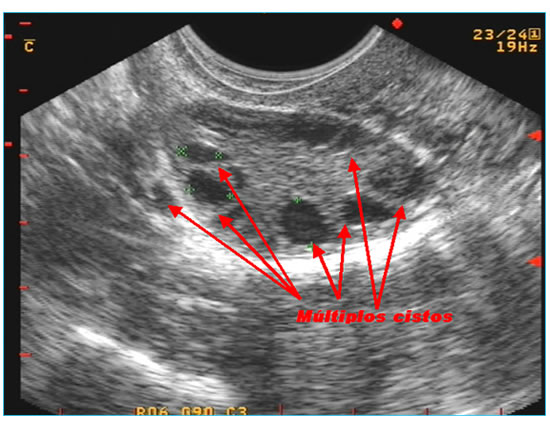

Cistos de ovários são óvulos em formação que não evoluíram durante sua transformação de células germinativas, para óvulos maduros. No quadro abaixo vemos inúmeros cistos em um ovário de uma garota de 17 anos